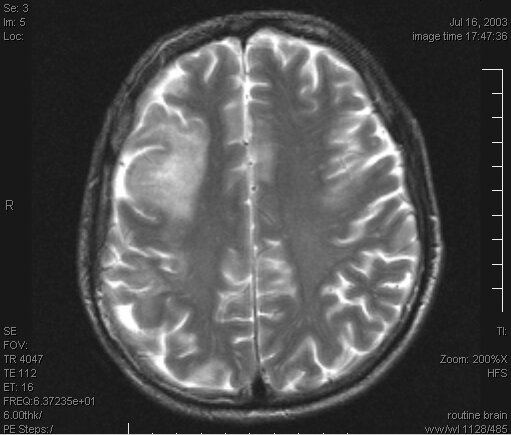

40-year-old woman with recently diagnosed advanced HIV infection is evaluated for altered mental status and hemianopia. Brain MRI is performed.

What is progressive multifocal leukoencephalopathy?